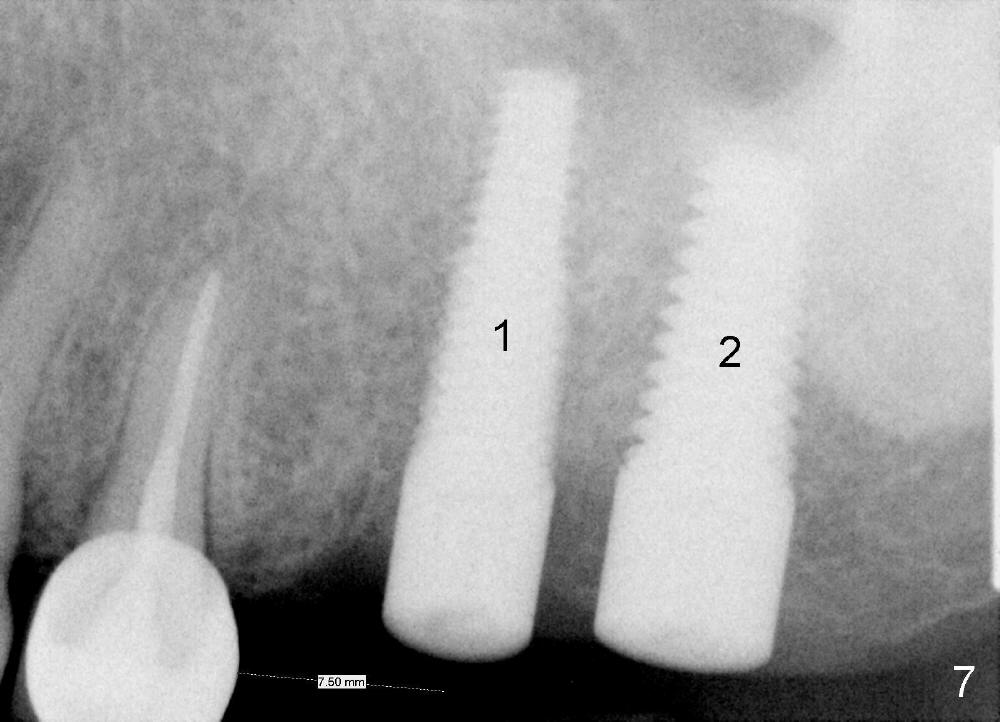

In fact, the implant at the 1st molar is planned to be placed 5.5 mm from the distal surface of the 2nd premolar (Fig.5). When the 1st intraop PA is taken with a 4.5x20 mm tap (Fig.6: T), the deviation is not noted (Fig.6: 7.5 mm vs. 5.5 mm in Fig.5). The trajectory of the implant (5x20 mm) remains deviated (Fig.7).

The trajectory should be corrected as early as possible and by changing the direction (Fig.8: from black line to red one). It should be not so difficult because of soft bone in the posterior maxilla and the mesiobuccal socket space (Fig.6 between arrowheads). It should be not too late to change the trajectory of an implant just placed.